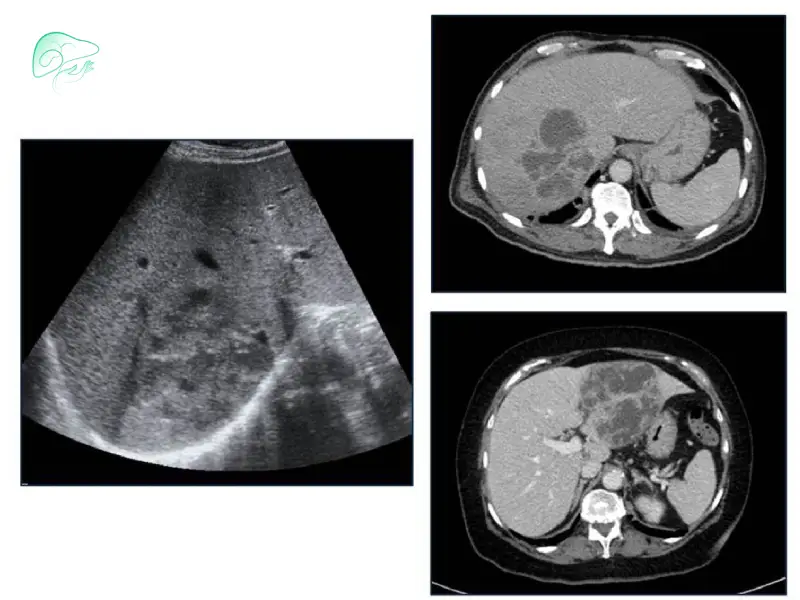

• سونوگرافی کبد: اولین و اصلی‌ترین روش بررسی سایز و شکل کیست است. غیرتهاجمی و سریع بوده و برای پیگیری دوره‌ای کیست‌های کوچک یا بدون علامت مناسب است.

• سی‌تی‌اسکن و MRI با کنتراست: برای کیست‌های بزرگ، پیچیده، دارای ویژگی‌های مشکوک یا رشد سریع استفاده می‌شوند. این روش‌ها جزئیات دقیق دیواره، سپتوم‌ها و ندول‌ها را نشان می‌دهند و به تشخیص احتمالی بدخیمی کمک می‌کنند.